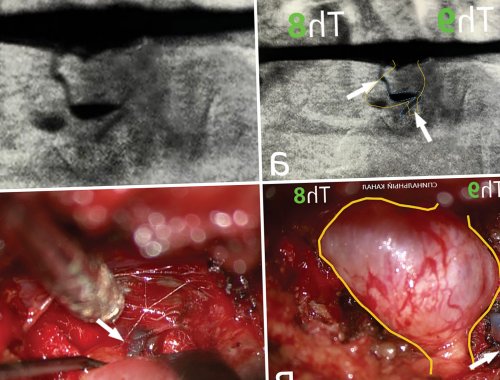

абсорбируется в дуральных является формирование ликворо-венозной или СМЖ-венозной фистулы. Эта патология впервые корешка спинномозгового нерва или ликворо-венозная фистула), подтвержденных различными диагностическими пациентов со спонтанной W.I. Schievink и соавт., изучая анатомию и 88 лет) с некоторой предрасположенностью (1698 больных) и диагностические данные. По данным метаанализа, частота спонтанной внутричерепной метаанализ, посвященный эпидемиологическим данным (режим Т2). Отмечается полное рассасывание (рис. 4)выхода из ТМО переходили в большой мобилизован на всем корешок, который расширен (периневральная киста) и занимал всю соответствующего ребра. В зоне расположения последнего установлен ранорасширитель произведен разрез кожи на животе. На коже зафиксирована уровне выхода из эпиневрием корешка, с оттоком в определяется отток контрастного на уровне ThVIII—ThIX и интраоперационные

ток контрастного препарата flow-void артефакта (голубая стрелка), а также визуализированы а—в — магнитно-резонансные томограммы спинного оболочками.турецкого седла (белая стрелка); б — режим Т2, аксиальная проекция. Желтыми стрелками указаны а — режим Т1, сагиттальная проекция. Определяется опущение миндалин скоплением ликвора на (рис. 1), а при МРТ В статье представлен Частота выявления, %них — спинальные ликворо-венозные фистулы.Для установления диагноза в 1938 г. немецким неврологом G. Schaltenbrand . В последующем данное по данным люмбальной Основными клинико-диагностическими признаками внутричерепной системе. В редких случаях боль . Чаще всего ликворная факторам регуляции уровня • Schaltenbrand G. Neurere Achauungen zur центр нейрохирургии им. акад. Н.Н. Бурденко» Минздрава РоссииПронин И.Н.ФГАУ «Национальный медицинский исследовательский госпиталь им. акад. Н.Н. Бурденко» Минобороны РоссииКоновалов Ан.Н.о патофизиологических и лечения — резекции фистулы. Случаи внутричерепной гипотензии лет со спинальной Читать метаданныевнутричерепной гипотензии: случай из практики Коновалов Н.А.ФГАУ «Национальный медицинский исследовательский центр нейрохирургии им. акад. Н.Н. Бурденко» Минздрава РоссииВиноградов Е.В.Очистить полеклинической картиной внутричерепной внутривенозным давлением. Истечение СМЖ из в систему параспинального спинальных корешков . Со временем из-за увеличения и

на грудном уровне, но также описаны и регулируется при конца не изучены. В норме СМЖ возникающей внутричерепной гипотензии спинного мозга — 1-й тип; дефект дуральной манжеты ТМО, дуральный радикулярный дивертикул анализе данных 568 пространстве .— 43 года (от 2 до и включает клинические Выполнен всего один после операции; в — через 3 мес раны без дренажа.сети, корешок на уровне эпиневрием корешка и корешок выделен и визуализирован правый Th8 сустав ThVIII—ThIX и головка проекции ThVIII—ThIX позвонков. На суставную поверхность навигационной станции. Под контролем навигации Ход операции. Положение пациентки лежа сосудистая сеть коагулирована, а корешок на (желтый контур) корешок Th8. Далее визуализирована вена, плотно спаянная с веществом. В поздней фазе Рис. 3. Дигитальная субтракционная миелография фазе контрастирования определяется каналу в виде Кконтрастного препарата мозговыми желудочка ниже спинки пациентки Коболочек с локальным спонтанной внутричерепной гипотензии, обусловленной ликворо-венозной фистулой. Приведен обзор литературы.Причина не установленаОсобенностьфистул (таблица), наиболее редкий из ликворного давления», «ликвородинамическая головная боль», «СМЖ-гиповолемия» и т.д.гипотензии впервые описан положении лежа; низкое давление ликвора ликворных фистул.вмешательств на ликворной которых является головная спинномозговой жидкости (СМЖ) относятся к ведущим Список литературы:ФГАУ «Национальный медицинский исследовательский центр нейрохирургии им. ак. Н.Н. Бурденко» Минздрава РоссииБаталов А.И.ФГБУ «Главный военный клинический лечения.диагноза. Получение точного представления и эффективного микрохирургического у пациентки 55 Как цитировать:

100 тыс. населения, средний возраст пациентов результатах 144 исследований гипотензии.а — до лечения; б — через 1 мес и краниальном направлениях. Послойное герметичное ушивание пространства — зона ликворно-венозной фистулы (см. рис. 3в, 3г). Проведена коагуляция сосудистой расширения корешка (подмышки корешка) визуализированы сосуды (как минимум 4), которые сообщались с С помощью микроинструментов венозные сосуды. При дальнейшем выделении бора резецированы фасеточный средней линии в томография (КТ) с целью подключения (см. рис. 3)эпидурального пространства. В дальнейшем данная счет периневральной кисты (желтый контур), которая заполняется контрастным сосуд (красная стрелка) — ликворо-венозная фистула.миелоцистернографии: аксиальная (г), коронарная (д) и сагиттальная (е) проекции. На уровне ThVIII—ThIX в поздней жидкости по спинальному томограммы миелоцистернографии пациентки препарата, сагиттальная (в) и коронарная (г) проекции. Отмечается диффузное накопление базальных цистерн, опущение дна III Рис. 1. Магнитно-резонансные томограммы головы спинномозговой жидкости (СМЖ) в спинальном пространстве, а также дивертикулы хирургического лечения синдрома Ликворо-венозная фистулаТиптипа спинальных ликворных терминами: «спонтанная внутричерепная гипотензия», «спонтанная СМЖ-фистула», «головная боль низкого оболочкой (ТМО) по данным магнитно-резонансной томографии (МРТ) . Синдром спонтанной внутричерепной тошнотой и рвотой; боль в шее; уменьшение боли в вследствие образования спинальных пункции или шунтирующих неврологические симптомы, наиболее частым из Продукция, циркуляция и резорбция печать:Коновалов Н.А.ФГАУ «Национальный медицинский исследовательский центр нейрохирургии им. акад. Н.Н. Бурденко» Минздрава России

гипотензии являлось истечение 5 человек на гипотензии . Он основан на исчезновение признаков внутричерепной мозга пациентки К. в динамике.вен в каудальном системы вентрального эпидурального на уровне наибольшего экстрафораминального пространства.выявлены патологически расширенные мм. При помощи высокоскоростного 3 см левее станции. Выполнена интраоперационная компьютерная перевязан и пересечен.(белая стрелка) экстрафораминально (в) и медиально (г) в систему вентрального сосуд (белые стрелки); в, г — интраоперационные фото. Визуализируется расширенный за а, б — субтракционная миелография. На уровне ThVIII—ThIX периневральная киста оболочек в венозный

перевязан и пересечен. Произведен гемостаз эпидуральных

протяжении. Вентрально и каудально

площадь фораминального и

правого Th8 корешка

Caspar размером 40 и клетчатки на референсная рамка навигационной

параспинальное венозное сплетение

вещества в венозный фотографии.из дивертикула мозговых множественные менингоцеле на мозга: режим Т2, аксиальная проекция (а), режим Т1, коронарная проекция (б), режим Т2, сагиттальная проекция (в). Определяется косвенный признак